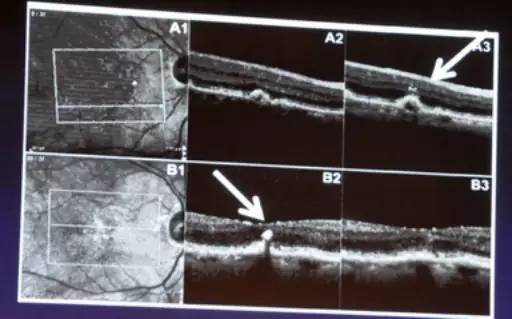

AMD患者常伴发PED(视网膜色素上皮与Bruch膜之间分离)。PED分为玻璃膜疣样PED,浆液性PED和纤维血管性PED。OCT显示玻璃膜疣样PED在黄斑区均匀的条索状高反射物质沉积及波浪状高反射RPE带,浆液性PED为黄斑区均匀的低反射物质沉积及平滑的RPE层隆起,而纤维血管性PED显示黄斑区不均匀的高反射物质上覆盖不规则RPE层(图2)。

图2. PED分类及OCT表现